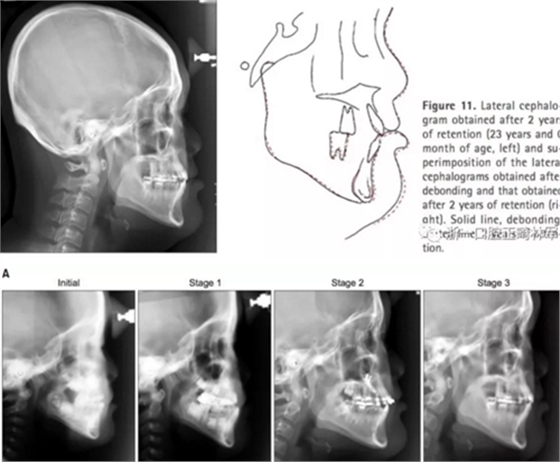

2年后隨訪提示治療結(jié)果得到保持(圖10,11,表1-3),不同階段的頭側(cè)重疊結(jié)果見圖12。